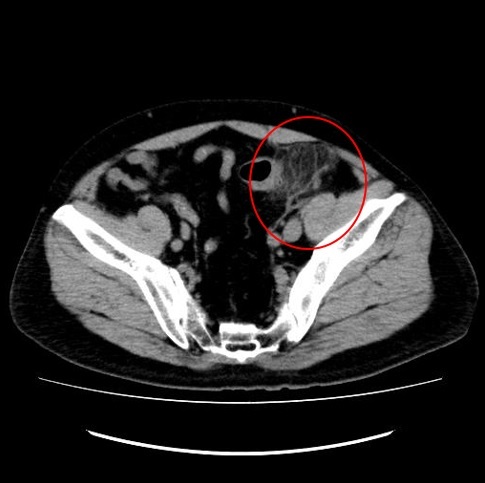

例5 憩室炎